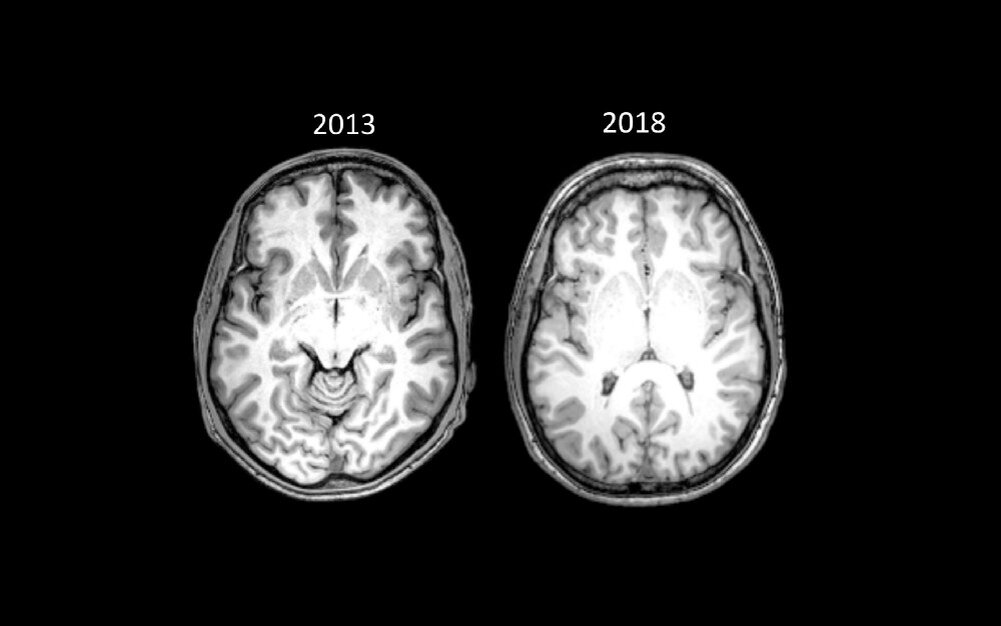

Изображения мозга ниже - это сканированные изображения головного мозга Брайана. Тот, что слева, был заснят в рамках исследования в 2013 году, когда Пенни только бросил наркотики после 15 лет зависимости. Снимок справа был сделан в мае 2018 года в рамках документального фильма о стрессе.

Снимки мозга, сделанные в 2013 и 2018 годах. Фотографии содержат срез, показывающий переднюю спайку, стандартную анатомическую структуру, используемую для сравнения снимков головного мозга.